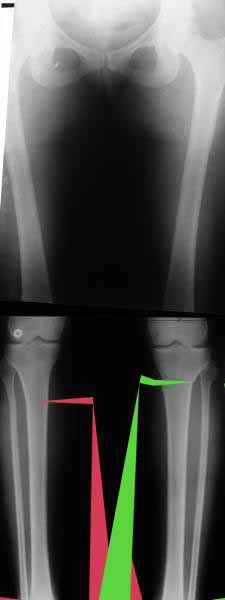

Из приведнной схемы не совсеим понял что означают разноцветные линии.

И зачем латерализация периферического фрагмента. Я всегда делаю медиализацию. См схему. И для данного случая медиализация подходит как нельзя лучше.

a> Я всегда делаю медиализацию. См схему. И для данного случая

Медиализация - это чисто эстетический прием, как я понимаю. Поскольку если делать остеотомию ниже вершины деформации, для восстановления оси надо делать смещение по ширине, в данном случае как раз латерализацию.

А вот на схемке без осей - там на разных уровнях (который правильнее?) устранение варуса чисто открытым клином без медиализации-латерализации. Если как-то так сделать - этого недостаточно будет?

Мне представляется оптимальным на уровне 3-4 линии (т.е. как раз посредине отмеченной зоны). Если рассчимтываешь делать медиализацию, то параллельно суставной поверхности, иначе просто не сдвинешь без джистракции - отломки зацепятся. Если без медиализации - то вообще не имеет значения.